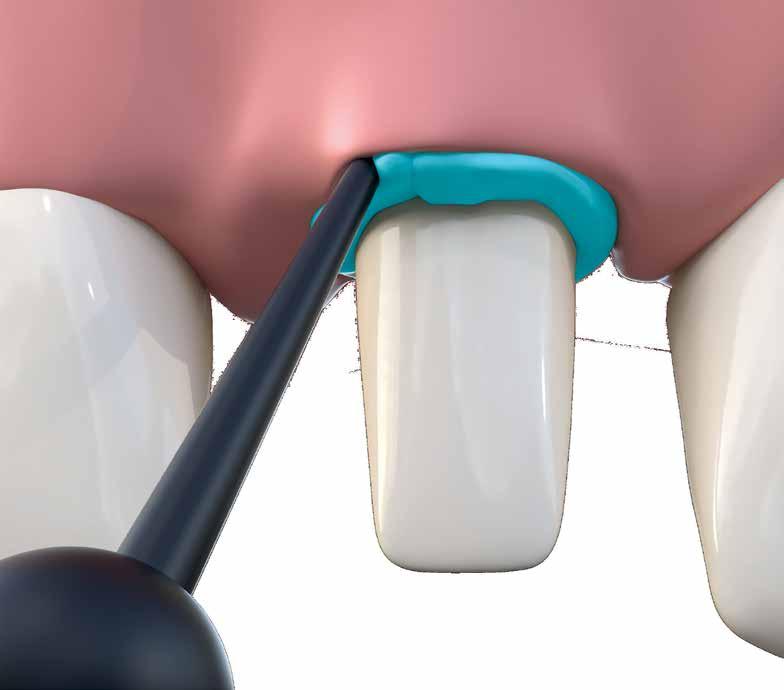

Figure 4. Placement of the unitary transepithelial after the second phase at 5 months for progressive loading of the implant.

Figure 2 Figure 3 Figure 4 Figure 1

Figures 5-6 Clinical images of the patient at the time of crown placement. Figure 7. Radiographic image at 4 years of follow-up showing the bone stability of the implant and the rehabilitation.